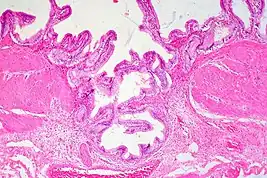

Adenomyomatosis is frequently associated with gallstones and is often diagnosed incidentally, either from a cholecystectomy specimen or autopsy.[4][5][6] No serologic test exists to specify adenomyomatosis and laboratory studies are often normal. Co-existing diseases like cholecystitis may result in abnormal test results, such as elevated levels of white blood cells (leukocytosis), liver enzymes (transaminitis), or bilirubin (hyperbilirubinemia).[5]

Ultrasound is the preferred initial diagnostic choice for suspected gallbladder disease. Several distinct features of adenomyomatosis are discernable using ultrasound, making it a reliable modality for diagnosis.[4][5][6] The most characteristic features seen on ultrasound are the Rokitansky-Aschoff sinuses, which present either as echogenic foci when filled with biliary sludge/gallstones or anechogenic foci when filled with normal bile.[4][5][6] Other key features that may be seen include wall thickening and ring-down artifacts known as "comet tails" (produced by reverberations of sound between the sinuses).[4][5][6] Ultrasound can also distinguish between diffuse, segmental, and localized variants of adenomyomatosis based on morphology.[5][6]

In some cases, gallbladder wall thickening may be seen on ultrasound but is poorly defined and lacking specificity, particularly if the characteristic Rokitansky-Aschoff sinuses are not visualized. This can make it difficult to distinguish adenomyomatosis from other conditions that result in gallbladder wall thickening such as gallbladder cancer.[4][5][6] In these cases, MRI can prove helpful in providing the resolution needed for diagnosis. Especially effective is the T2-weighted MRI at visualizing the pathognomonic Rokitansky-Aschoff sinuses, which appear as round-shaped hyperintense cystic spaces that align in a curvilinear fashion along the gallbladder wall in a pattern described as the ”pearl necklace sign”.[4][5][6]